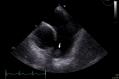

Decision-Making in a Pulmonary Valve Fibroelastoma: The Role of Intraoperative Transesophageal Echocardiography

Keywords: Cardiac fibroelastoma; Cardiac surgery; Cardiac tumor; Pulmonary valve; Transesophageal echocardiography.